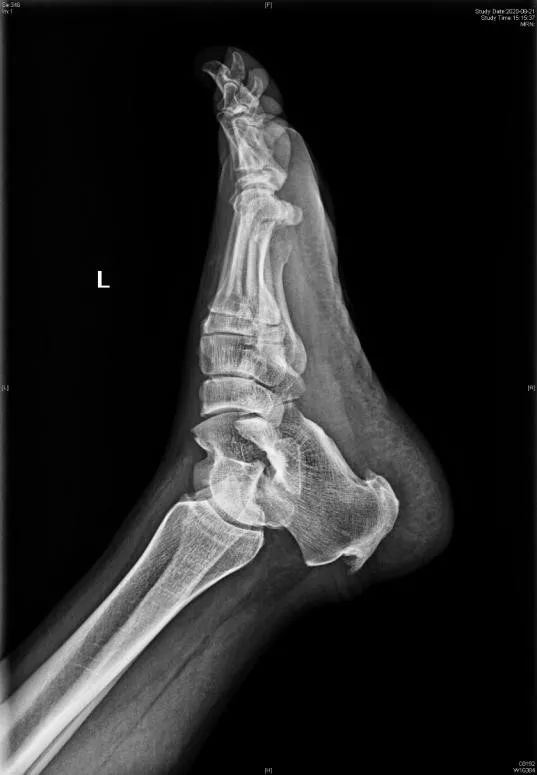

X:Fowler and Philips angle,44°-69°

CLA角:Chauveaux-Liet  Angle,CLA=α-β,>12°怀疑,X/Y值:<2.5高度怀疑

FPA和PPL不可靠,Haglund综合征与跟腱钙化和跟骨后方骨刺关系密切。

X/Y由小于2.5到大于2.5